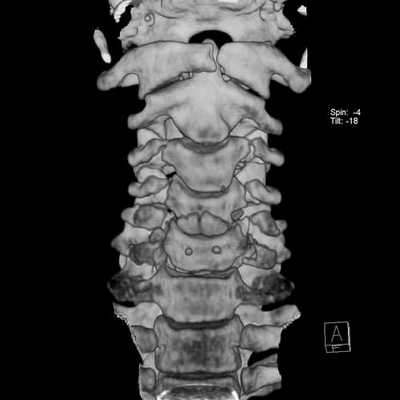

Шейный отдел позвоночника отличается от других большой физиологической подвижностью и минимальной осевой нагрузкой. Ширина позвоночного канала в шейном отделе также существенно меньше чем в нижележащих. В то же время, в шейном отделе рано проявляется спондилез - комплекс дегенеративных изменений в виде обызвествления связок, краевого остеофитоза, артроза дугоотростчатых суставов и унко-вертебральных сочленений. Грыжи дисков в шейном отделе редко бывают большие и медиальные. Хотя при таких грыжах может быть смещение и даже сдавление спинного мозга, они долго протекают бессимптомно. Большинство грыж парамедиальные, которые сопровождаются остеофитами, формируя “твердые” грыжи. При МРТ шейного отдела позвоночника видно, что они часто двухсторонние, сдавливают передний корешок, вызывая типичную корешковую боль вдоль руки. Особенно коварны боковые (фораминальные) грыжи, так как они не всегда отчетливо видны при МРТ шейного отдела позвоночника. Особенно надо отметить, что в шейном отделе позвоночника слабо развита эпидуральная жировая клетчатка, что усложняет визуализацию грыж в аксиальной плоскости на Т2-взвешенных МРТ. Градиентные аксиальные МРТ шейного отдела позвоночника лучше показывают корешок и его сдавление. Сдавление корешка на поперечных МРТ шейного отдела видно как его смещение, отек, стирание четкости границ и, иногда, расширение эпидуральной вены. Спондилез и грыжи дисков приводят к стенозу (сужению) позвоночного канала, нарушения кровообращения по эпидуральным венам и артериям спинного мозга, вызывая его локальный отек и изменения по типу миеломаляции. При МРТ позвоночника в таких случаях виден светлый участок на Т2-взвешенных МРТ. Состояние может быть обратимым, если вовремя оперирована грыжа или проведена сосудистая терапия. Тогда на МРТ нейного отдела позвоночника в сагиттальной плоскости высокий сигнал на Т2-взвешенных МРТ изображениях уменьшается или совсем исчезает. При МРТ в СПб этому симптому мы придаем особое значение, так как он связан с миелопатическим синдромом и говорит о необходимости неотложных лечебных мероприятий.